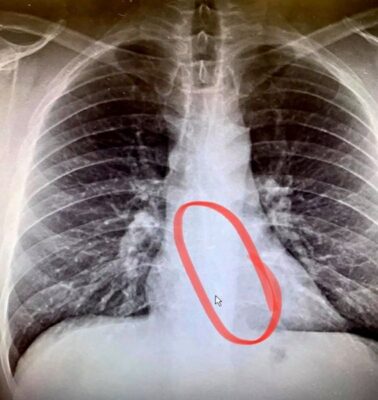

엑스레이 사진을 찍어본 결과, 사라진 무선 이어폰이 그의 식도 하단에 걸려있었다.

그는 응급 내시경 시술로 약 2인치(약 5㎝) 길이의 이어폰을 빼낼 수 있었고, 다행히 크게 다친 곳도 없었다.